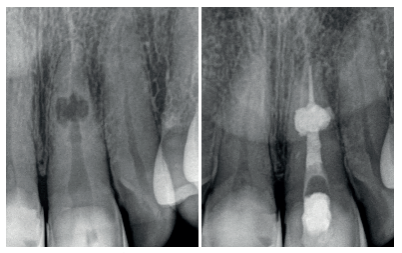

En una segunda sesión y con el conducto libre de tejido inflamatorio, se confirma la longitud de trabajo (22 mm) con una lima 10 K-file (Dentsply Maillefer, Ballaigues, Switzerland). Se instrumenta hasta X2 (25.06) de Protaper Next (Dentsply Maillefer, Ballaigues, Switzerland) y se realiza el protocolo de irrigación final: NaOCL 2,5% EDTA 17% NaOCL 2,5%. Ambos irrigantes fueron activados de manera hidrodinámica con la lima Xp-Finisher (Fkg Dentaire, La ChauxdeFonds, Switzerland) de diámetro 25 sin conicidad, a una velocidad 1000 rpm y torque de 1Nw. Se procede al secado intraconducto con puntas de papel del número 25 (Dentsply Maillefer, Ballaigues, Switzerland), donde se puede apreciar la diferencia entre el conducto y la perforación hacia vestibular (Figura 4). A continuación, se realiza una conometría con gutapercha calibrada tipo Autofit del 6% (Kavo-Kerr, California, Estados Unidos), comprobando la existencia de un correcto stop apical.

Para poder sellar de manera ortógrada se realizó una técnica híbrida descrita en la literatura12 , consistiendo en obturar la parte apical a la reabsorción con gutapercha, la zona de la reabsorción con un material biocerámico y el tercio coronal con gutapercha de nuevo. Se utilizó como cemento sellador AH Plus (Dentsply Maillefer, Ballaigues, Switzerland) con el cono maestro calibrado (25.06), realizando condensación vertical en el tercio apical, con la unidad alpha del sistema B&L (B&L Biotech, Fairfax, Estados Unidos). Obturados los últimos 4 mm, se procedió a adaptar el material biocerámico ProRoot MTA blanco (Dentsply Maillefer, Ballaigues, Switzerland) en la zona reabsortiva con la ayuda de diferentes pluggers manuales 35/70, 40/80, 50/100 (B&L Biotech, Fairfax, Estados Unidos) y vibración indirecta13, consiguiendo un mejor relleno de la cavidad reabsortiva. El tercio coronal a la reabsorción se obturó mediante la técnica de inyección con la pistola β de la marca B&L.

El sellado del límite amelocementario se realizó con un vidrio ionómero reforzado con resina (Ionoseal, Voco, Cuxhaven, Alemania), para evitar posibles riesgos de filtración coronaria, hasta que la paciente volviese con su referidor para la restauración definitiva (Figuras 5 y 6).

Se realizaron revisiones a los 6, 12, 18 y 26 meses, encontrándose la paciente totalmente asintomática, con signos de curación en los tejidos periapicales, observándose una regeneración ósea completa en la cortical vestibular (ausente en radiografia inicial). A los 26 meses se le dio el alta y se remitieron al referidor todas las pruebas diagnósticas y radiológicas (Figura 7).